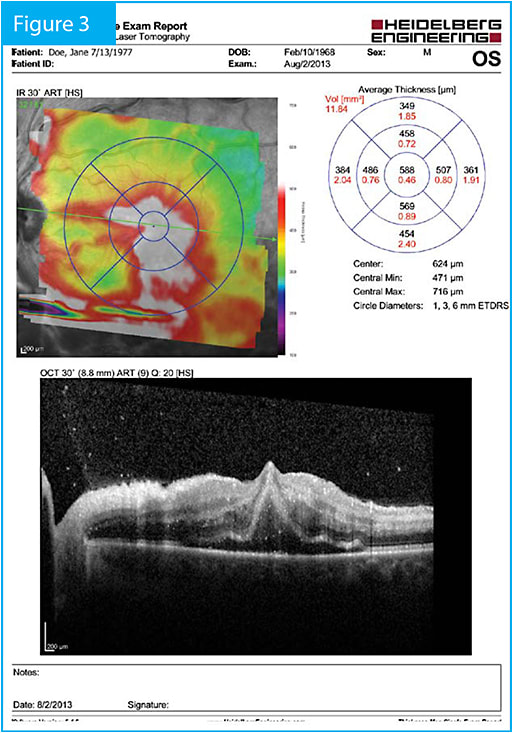

Figure 4. Six months after initiation of therapy with a dexamethasone implant and an anti-VEGF injection, 1 month after a peripheral laser treatment, macular edema remained completely resolved.

The patient returned for monthly follow-up visits, receiving four additional anti-VEGF injections. By the first follow-up visit, central retinal thickness had decreased to 153 µm. Five months after the initial visit, extreme ischemia, which is known to up-regulate VEGF, was still present, so the patient received peripheral laser treatment, which was his last treatment of any type to date. As of 1 month post laser (6 months after presentation), the macular edema remained completely resolved and visual acuity had improved to 20/50.